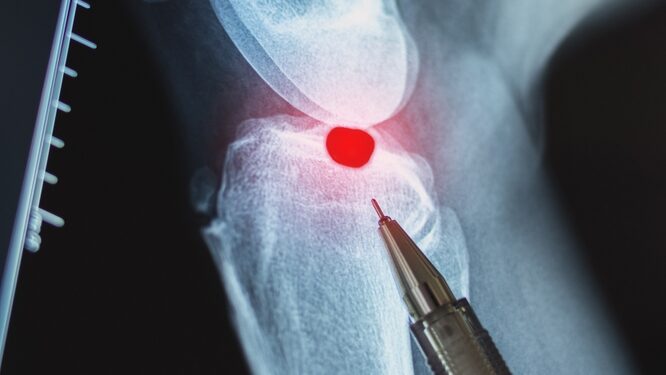

Nustačius įtartiną kaulinį iškilimą, gydytojas pirmiausia atliks apžiūrą ir išklausinės apie patiriamus pojūčius. Diagnozę patvirtinti dažniausiai padeda vaizdiniai tyrimai:

- Rentgenogramos;

- Kompiuterinė tomografija (KT);

- Magnetinio rezonanso tomografija (MRT).